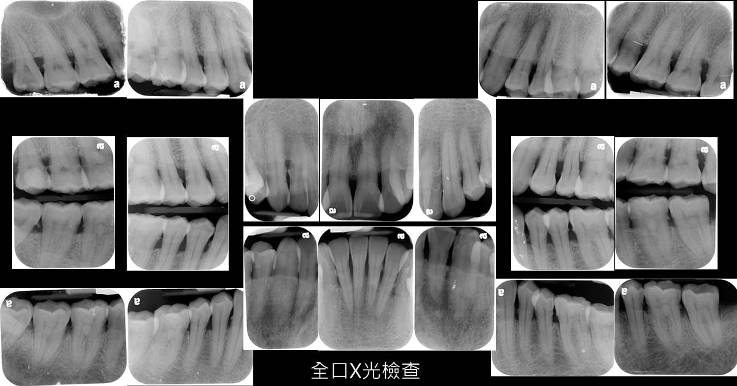

全口X光攝影

X光片可以了解牙齒周邊骨頭的高低,因為隨著牙周發炎的進展,會造成牙齒周邊骨頭的流失,牙醫師藉由X光片判讀目前牙齒周邊骨頭的形態、牙齒有沒有蛀牙、不良的假牙、牙根尖發炎等問題。

全口X光片的拍攝,依治療的需求,可能會需要14至18張X光片的拍攝。